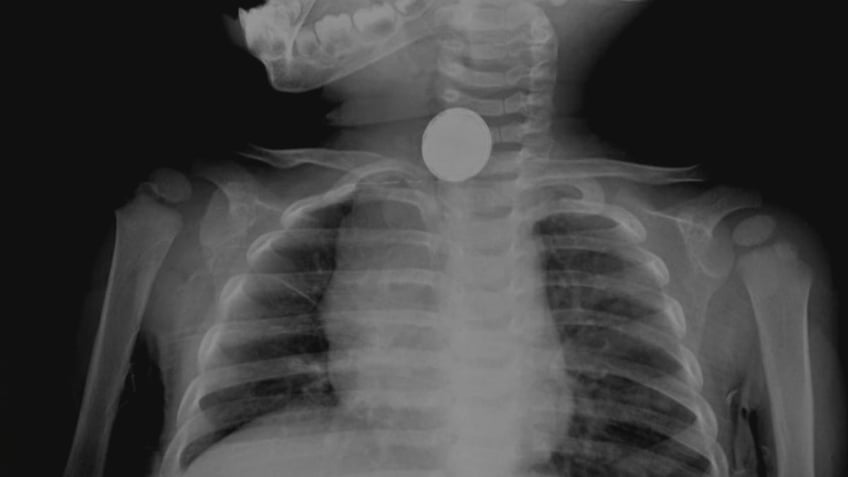

Foreign objects lodged in the human body can cause ‘serious injury,’ Dr. Marc Siegel warns

Foreign objects lodged in people’s bodies was the ninth leading cause of unintentional injuries that led to emergency room visits in 2021, according to data from the Centers for Disease Control and Prevention (CDC) — with nearly 278,000 U.S. adults seeking care.

"Serious injury can result."

"Foreign objects in people’s bodies" was the ninth leading cause of unintentional injuries that led to emergency room visits in 2021, according to data from the CDC. (iStock)